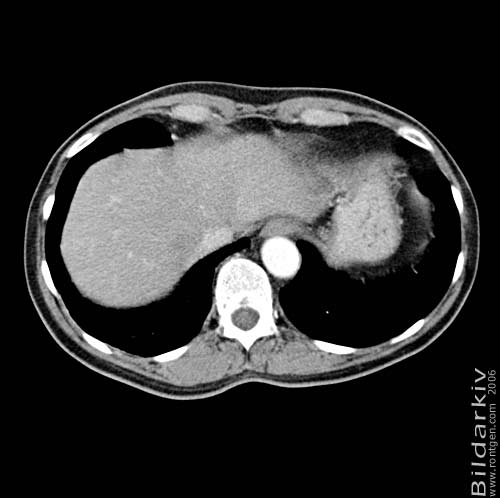

Thorax 48

Snitt över thorax med kontrast. Sk. mediastinum-fönstersättning.

CT Röntgen Helsingborgs lasarett

Mediastinum